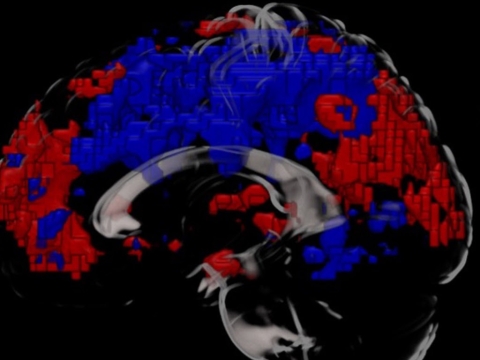

Layers of the MRI scan also showing increased activity in the medial prefrontal cortex and parietal cortex

MRI scan of the brain showing the parietal cortex (left) and medial prefrontal cortex (right) as red after a cold water bath - indicating increased activity compared to the areas showing in blue

Comparing the scans showed that changes had occurred in the connectivity between specific parts of the brain, in particular, the medial prefrontal cortex and the parietal cortex.

“These are the parts of the brain that control our emotions, and help us stay attentive and make decisions,” Dr Yankouskaya said. “So when the participants told us that they felt more alert, excited and generally better after their cold bath, we expected to see changes to the connectivity between those parts. And that is exactly what we found.”